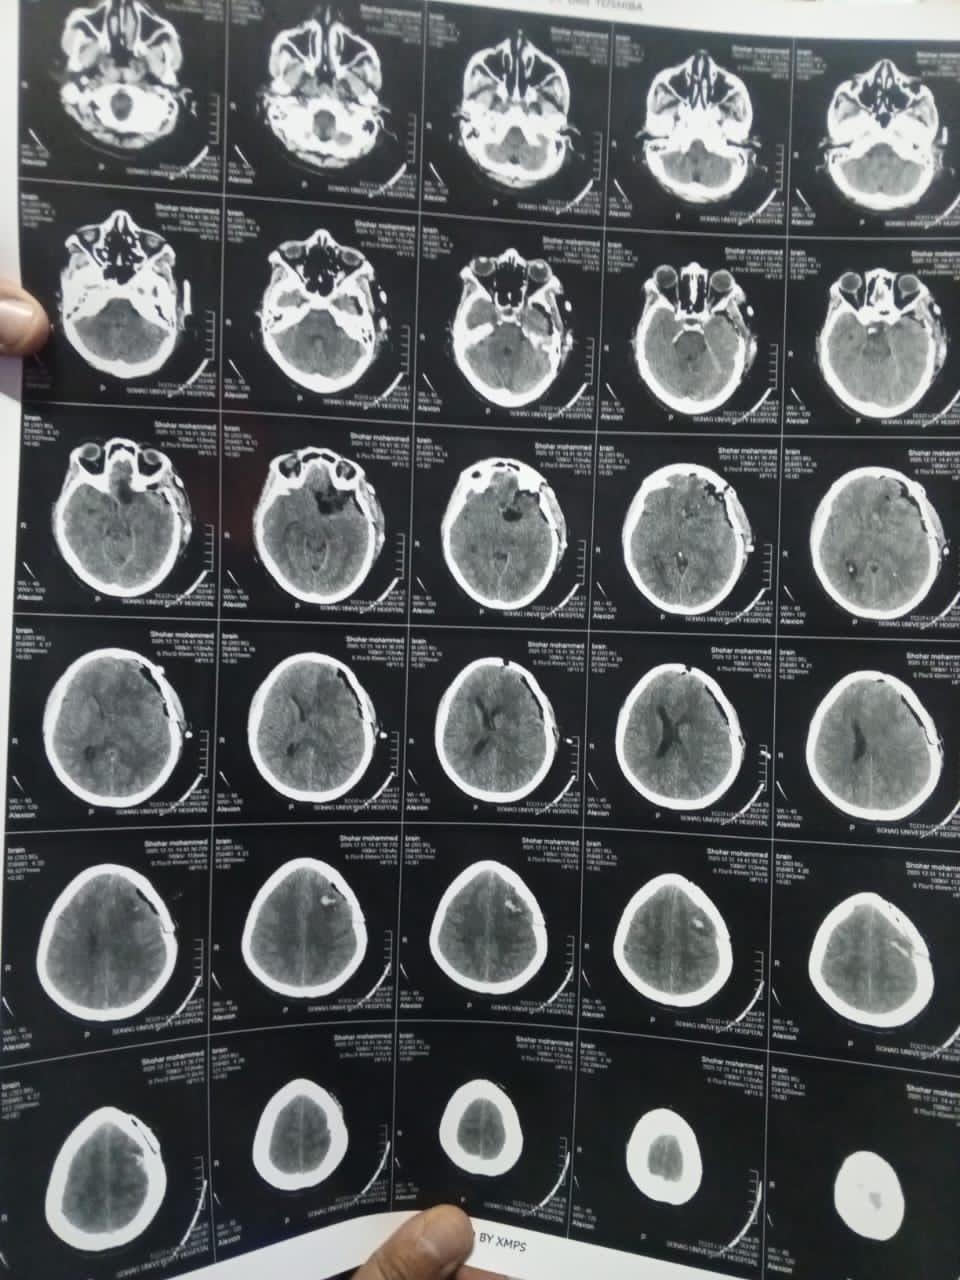

ومن جانبه، أوضح الدكتور مجدي القاضي، عميد كلية الطب البشري، ورئيس مجلس إدارة المستشفيات الجامعية ، أن المريضة حضرت وهي تعاني من صداع شديد وارتفاع بضغط المخ مع تدهور ملحوظ في حدة الإبصار، وبإجراء الفحوصات الطبية اللازمة وأشعة الرنين المغناطيسي، تبيّن وجود ورم كبير بقاع الجمجمة ضاغط على أعصاب البصر والأوعية الدموية المغذية للمخ، ما استدعى التدخل الجراحي العاجل باستخدام أحدث التقنيات الدقيقة.